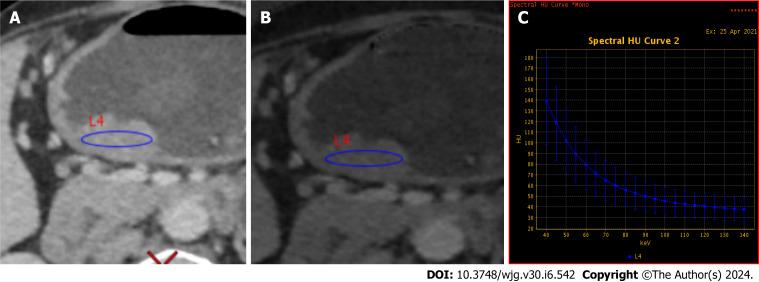

RESULTS

In both the training and validation cohorts, CT T3-4 stage, CT-N positive status, and CT-EMVI positive status are more prevalent in the LVI/PNI-positive group and these differences are statistically significant ( < 0.05). LR analysis of the training group showed preoperative CT-T stage, CT-EMVI, single-energy CT values of 70 keV of venous phase (VP-70 keV), and the ratio of standardized iodine concentration of equilibrium phase (EP-NIC) were independent influencing factors. The AUCs of VP-70 keV and EP-NIC were 0.888 and 0.824, respectively, which were slightly greater than those of CT-T and CT-EMVI (AUC = 0.793, 0.762). The nomogram combining CT-T stage, CT-EMVI, VP-70 keV and EP-NIC yielded AUCs of 0.918 (0.866-0.954) and 0.874 (0.784-0.936) in the training and validation cohorts, which are significantly higher than using each of single independent factors ( < 0.05).